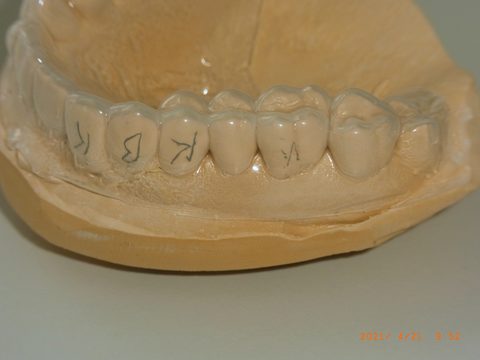

Das Gipsmodell nach der Alginatabformung bildet die Grundlage für Tiefziehschiene und den späteren KIL.

Die 1 mm dicke Tiefziehschiene (Copyplast, Fa. Scheu) überzieht das Gipsmodell gleichmäßig. Sie definiert später den Spalt für das mittelfließende Zweitabformmaterial.

Nahaufnahme: Die transparente Folie liegt den Zahnkonturen exakt an. Die durch das Tiefziehgerät hochgradig standardisierte Herstellung vermeidet interdentale Septen, die beim klassischen Indiv-Löffel beschnitten werden müssen.

Fertiger KIL (links) neben dem Gipsmodell mit aufgezogener Tiefziehfolie (rechts). Der Löffel wird bis zu einige Tage vor der Verwendung im Eigenlabor gefertigt. Beschnitten wird der KIL im späteren Stumpfbereich gar nicht; in den übrigen Bereichen oral und lingual mit einem scharfen Küchenmesser bis ins gingivale Drittel der Zähne.